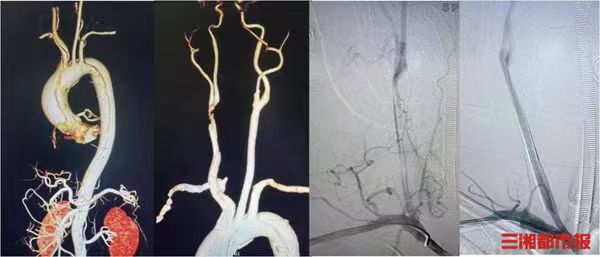

确定方案后,这场高难度的生死手术正式启动。凭借极致的精准操作,团队通过手术切开暴露桡动脉,成功建立介入治疗通路,顺利在堵死的右侧颈动脉里植入2枚支架,把被夹层压扁的血管完全撑开。术后造影显示,患者右侧大脑的血流瞬间恢复通畅,第一关圆满成功。

神经介入手术收尾的瞬间,宋国宝教授团队立刻无缝接力,开启第二关的心脏拆弹,并彻底拆除心脏上的致命“炸弹”。整场手术衔接流畅、零失误,两台高难度手术在同一间手术室、一次麻醉中全部完成,真正实现了“脑心同治”。